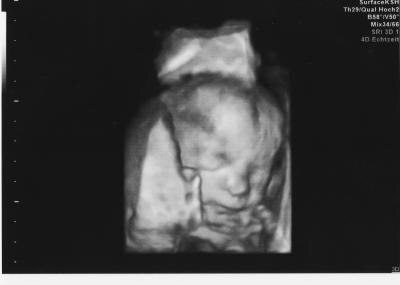

Hallo, bin gerade von der FD zurück. Habe mich den ganzen Tag aufgeregt und dann noch lange Wartezeit... aber es hat sich gelohnt. Es wurden keine Auffälligkeiten festgestellt, alles ist zeitgerecht entwickelt. Das Kleine wiegt etwa 520g und ist ca 22 cm groß. Und es gab endlich das langersehnte Outing.... Trommelwirbel taddaaaaa es wird ein Mädchen. Somit kann ich jetzt endlich hemmunglos shoppen gehen und bin heute Abend ein wirklich glücklicher Mensch. Liebe Grüße Jana

Bild zu Bericht FD + Outing - Forum für Februar - Mamis

Alles Gute zu deinem Mädchen und das alles in Ordnung is. Na dann lass dich mal nicht abhalten vom shoppen Das Foto sieht wunderschön aus. LG von Ute

Also das Bild ist ja wirklich waaaaahnsinnig süß!!! Soooo lieb!! Unglaublich!! Ich hab auch eins bekommen, aber das ist weit nicht so gut geworden...